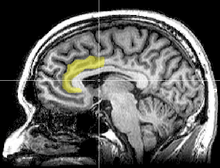

There is evidence suggesting that the more the anterior cingulate cortex signals conflict, the more dissonance a person experiences and the more their attitudes may change

Using functional magnetic resonance imaging (fMRI), Van Veen and colleagues investigated the neural basis of cognitive dissonance in a modified version of the classic induced compliance paradigm. While in the scanner, participants "argued" that the uncomfortable MRI environment was nevertheless a pleasant experience. The researchers replicated the basic induced compliance findings; participants in an experimental group enjoyed the scanner more than participants in a control group who simply were paid to make their argument.[64]

Importantly, responding counter-attitudinally activated the dorsal anterior cingulate cortex and the anterior insular cortex; furthermore, the degree to which these regions were activated predicted individual participants' degree of attitude change. Van Veen and colleagues argue that these findings support the original dissonance theory by Festinger, and support the "conflict theory" of anterior cingulate functioning.[64]